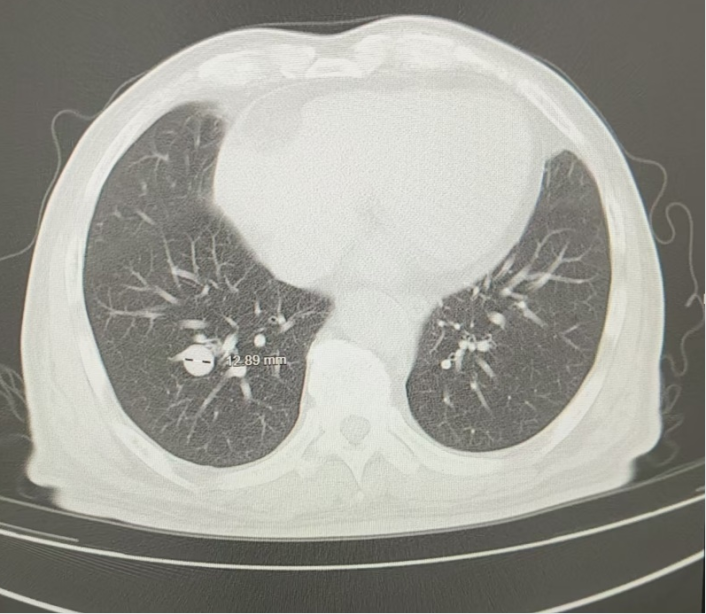

图2 患者治疗后2个月胸部影像学图像(2024年6月17日)

2024年6月(治疗后2个月),复查胸部CT:两肺多发结节,转移灶首拟,对比2024.4.16老片,两肺结节有所减小,疗效评估为部分缓解(PR);无明显并发症;肿瘤指标等生化检查结果良好;无明显药物副作用